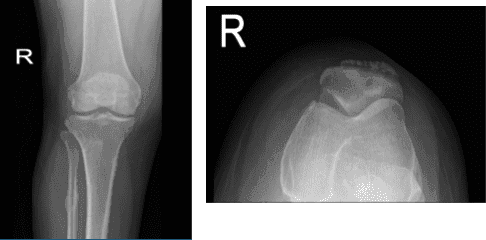

A 53 year-old female went to the office with her X-ray and complained of right knee pain for about weeks and she does not remember if it is from fall or injury, she has not gained weight, fever, chills. Upon the physical and X-ray examinations result, Sunrise patella, AP and lateral.

Distal femur, patella, proximal tibia and proximal fibula demonstrate intact cortical margins with no acute fracture. There is a suggestion for a healed fracture proximal shaft right fibula. There is mild narrowing of the medial joint compartment with slight osteophyte formation

There is spurring from the superior pole of patellar anteriorly. A joint effusion is present There is no radiographic evidence of soft tissue swelling. There are mild osteoarthritic degenerative changes. A joint effusion is present. There are no fractures.

Right knee X-ray AP and Lateral